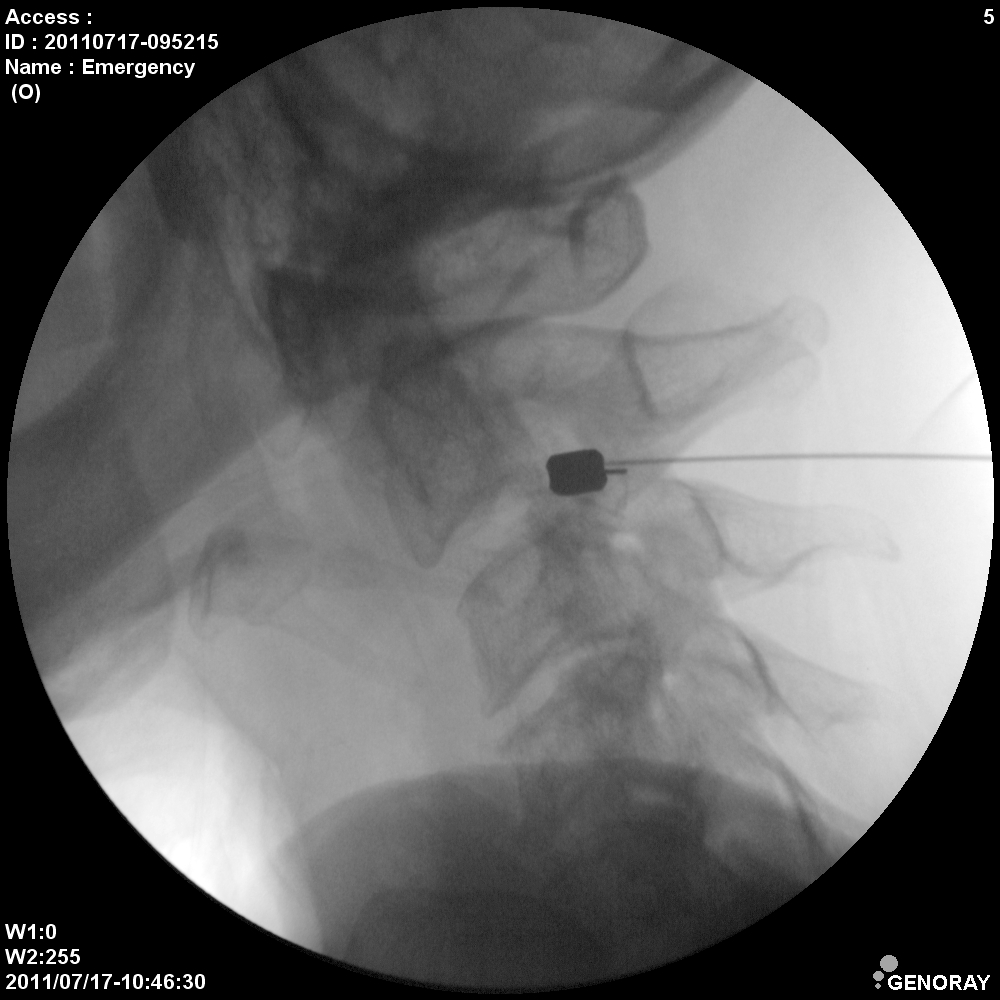

Аппарат применяется в различных областях медицины, таких как хирургия, ортопедия, педиатрия, травматология, урология и многих других. «АРХМ-РЕНЕКС» имеет широкий диапазон перемещений, легко позиционируется во всех направлениях, а так же имеет не большие габариты и вес обеспечивающие маневренность и простоту перемещений.

В качестве приемника используется усилитель рентгеновского изображения (УРИ) с ПЗС-матрицей 1024х1024 пикселей. Мощность рентгеновского питающего устройства 2,2 кВт.

- Непрерывная и импульсная рентгеноскопия с цифровой обработкой изображения.

- Цифровая рентгенография.